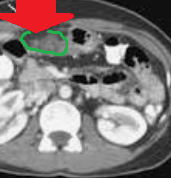

Εικόνες CT κοιλίας, που δείχνουν κυστικού τύπου βλάβη, μεταξύ ήπατος και ηπατικής καμπής του κόλου, σε επαφή με το εξωτερικό στρώμα του εντέρου, με πεπαχυσμένο τοίχωμα και χαμηλής πυκνότητας κέντρο (Ευγενική παραχώρηση Dr. V. Penopoulos)